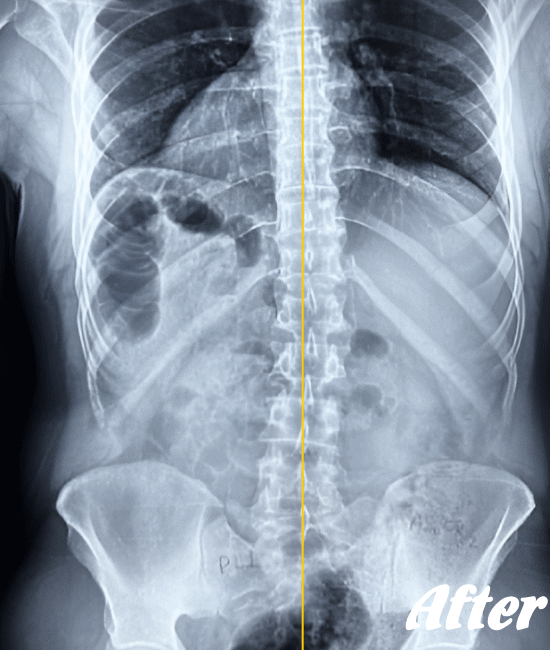

レントゲン、CT、MRIといった画像診断などで坐骨神経痛の原因となる病気(例えば、ヘルニアや脊柱管狭窄症など)が見つかれば、その治療を行います。原因となる病気が見つからない場合は、第一選択肢として、保存療法が適応されます。

HALOカイロプラクティック☆平和島整体院では、仙腸関節や腰、股関節などの部位を解剖学的に正しい状態へ戻すことで、筋肉をゆるめ、関節の詰まりを広げ、圧迫されてしまった神経を解放し、痛みや痺れのない状態へと回復させます。

また、首(頚椎)の歪みにより腰に負担がかかることで坐骨神経痛を発症することもあるため、首も調整します。

ただし、歩行に支障をきたすような激しい痛みの場合は、「股関節のズレが酷い」「腰椎の椎間が詰まっている」「ヘルニアが突出している」「仙腸関節が炎症を起こしている」…等々、通常よりも症状が悪化しているため施術回数が長引くことをご理解いただいたうえで、当院へお越し下さい。